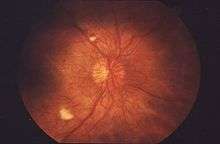

An ophthalmoscopic view of the retina showing advanced signs of diabetic retinopathy including two pale cotton wool spots.

Cotton wool spots are an abnormal finding on funduscopic exam of the retina of the eye. They appear as fluffy white patches on the retina. They are caused by damage to nerve fibers and are a result of accumulations of axoplasmic material within the nerve fiber layer. There is reduced axonal transport (and hence backlog and accumulation of intracellular products) within the nerves because of the ischemia. This then causes the nerve fibers to be damaged by swelling in the surface layer of the retina. A 1981 analysis concluded that "in most instances, cotton-wool spots do not represent the whole area of ischaemic inner retina but merely reflect the obstruction of axoplasmic flow in axons crossing into much larger ischaemic areas".[1] Associated findings include microvascular infarcts and hemorrhages. The appearance of cotton wool spots may decrease over time. Abundant cotton wool spots are seen in Malignant hypertension.